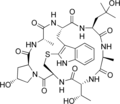

Phallisin Phallacidin

Phallacidin Phallacin